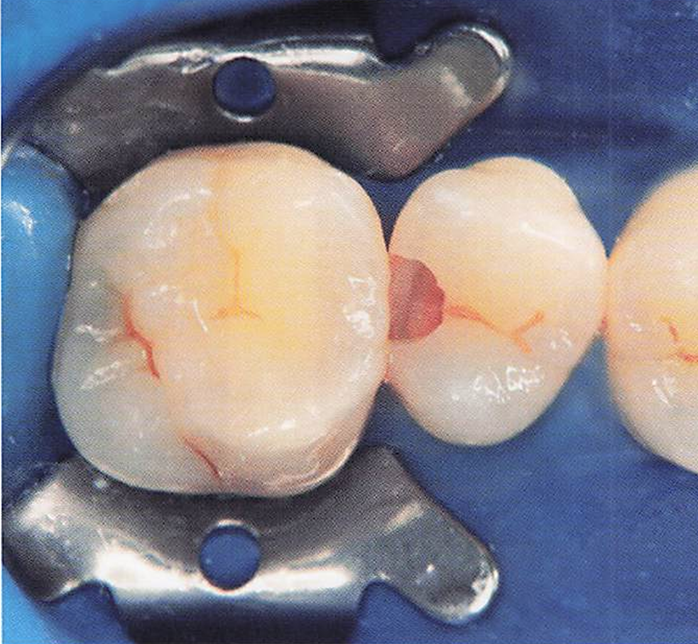

午前-41

23歳の男性。下顎左側第一大臼歯の冷水痛を主訴として来院した。 自発痛はないという。暫間的間接覆髄が行われることになった。水酸化カルシウム製剤貼付前の口腔内写真を別に示す。 この治療法を選択した目的はどれか。2つ選べ。

a.感染歯質の除去

b.歯髄組織の保護

c.軟化象牙質の再石灰化

d.デンティンブリッジ形成促進

解答を見る

b.c